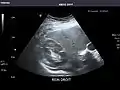

Kidneys: Right and left kidneys measure 11.5 cm and 12 cm in length respectively. No hydronephrosis. Small left lower pole kidney cyst.